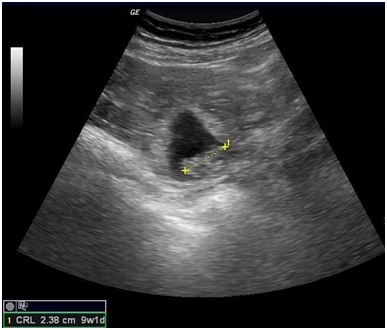

An urgent ultrasonography was done, which reported Single gestational sac with a foetal pole of 9weeks 1day in right adnexal region close to right ovary. Foetal cardiac activity was not present (Figure 1). Uterus was normal in size and echotexture with normal endometrial thickness (Figure 2a). Gross free fluid was noted in peritoneal cavity which on ultrasound guided aspiration came out to be blood suggesting hemoperitoneum (Figure 2b). Ultrasonographic features were consistent with ruptured right adnexal ectopic gestation with possibility of ruptured right ovarian ectopic pregnancy. Her initial blood results were Blood group B positive and Hemoglobin (Hb) 8.7 gm%.

Figure 1 Ultrasonography showing gestational sac with foetal pole of 9weeks 1day in right adnexa.